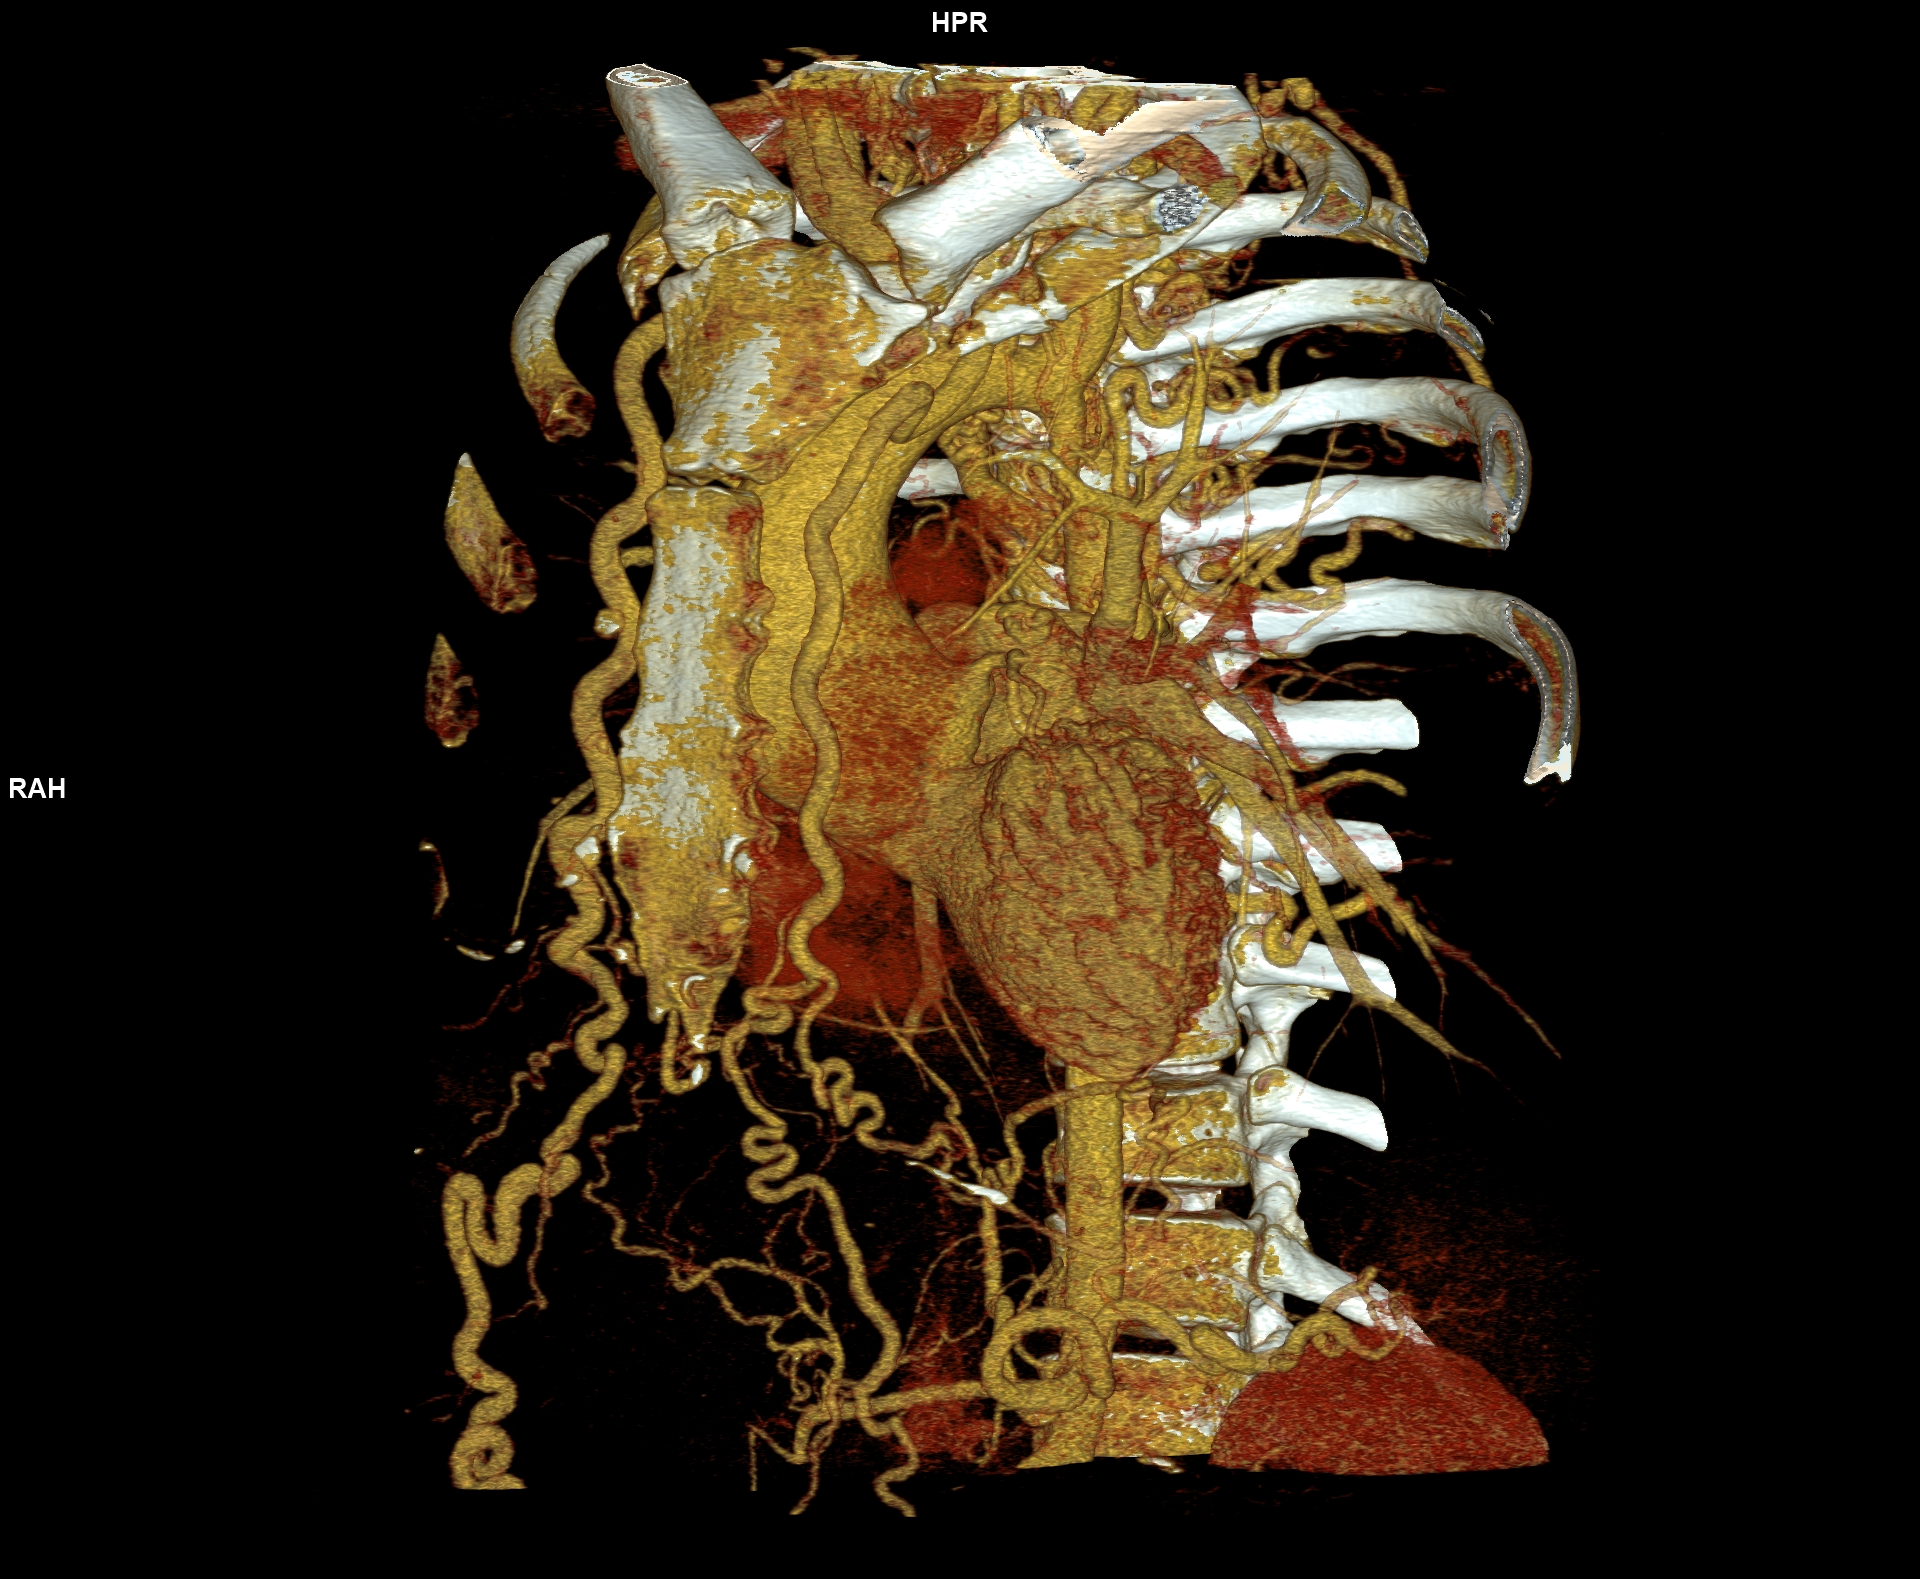

Figurile 6-10: reconstrucții volumice (VRT) din achiziție angioCT aorta toracică

Discuţie caz nr 109: Pacient cu suspiciune de coarctaţie de aortă – are indicație de angioCT aortă toracică; medicul radiolog la acești pacienți este indicat să efectueze investigația cu sincronizare ECG deoarece coarctaţia de aortă poate fi asociată și cu bicuspidie de valvă aortică, mai ales că la acest pacient ecografia cardiacă descria creștere de calibru a aortei ascendențe. Pe reconstrucția cine în planul valvei aortice din achiziția cardioCT cu sincronizare ECG se remarcă o valvă aortică morfologic tricuspidă, funcțional bicuspidă ce asociază ectazie de aortă ascendentă și coarctaţie de aortă descendentă cvasicompletă cu dezvoltare de circulație colaterală intercostală și mamară internă.